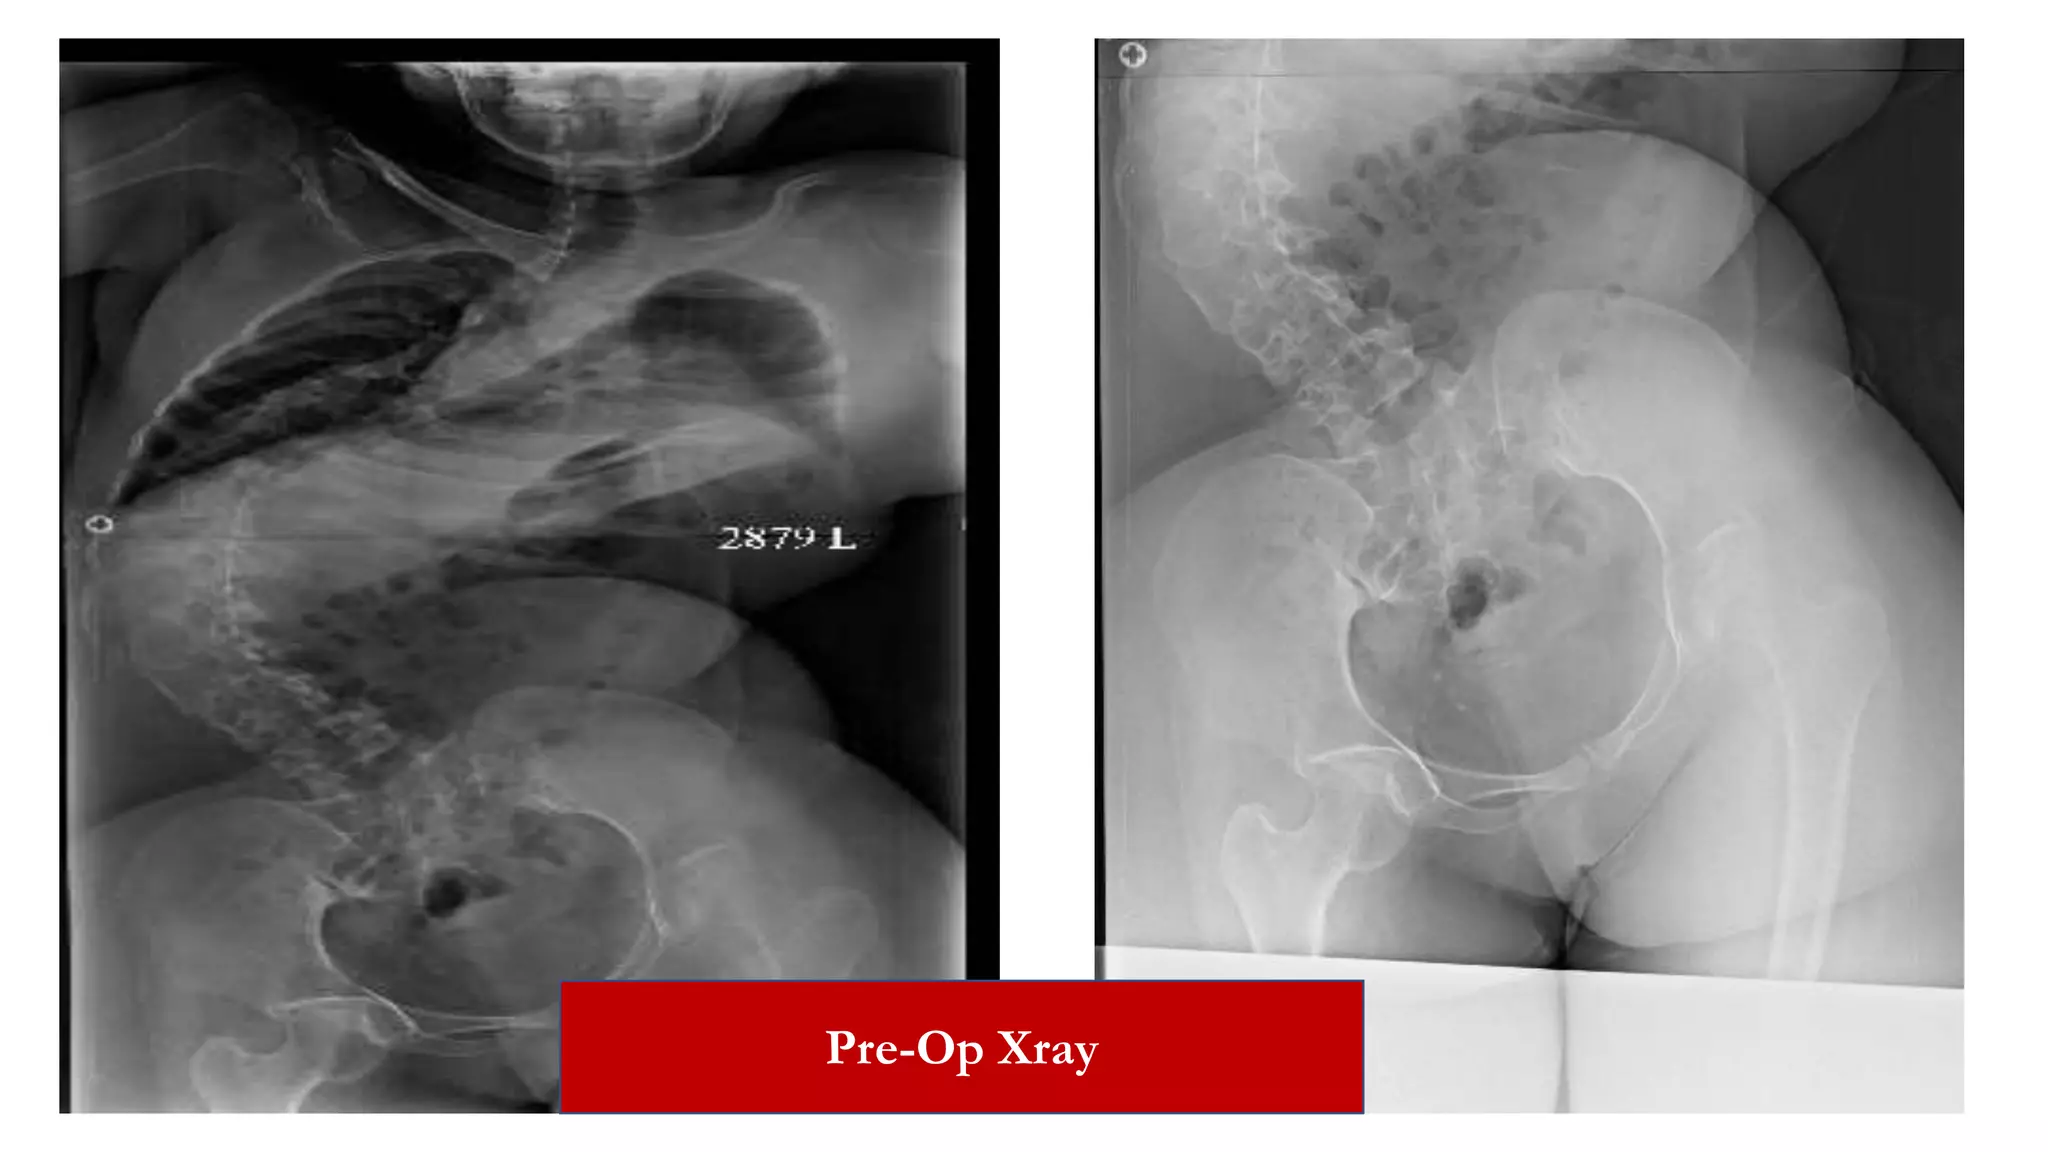

Pre-Op Xray

Case 1

• 17yr/Female.

• Progressive deformity of the back of 5 years duration.

• Normal birth and development. Twin has similar deformity.

• No history of trauma, respiratory symptoms or limb weakness.

• Diagnosis: Adolescent idiopathic thoracic scoliosis: Lenke Type I;

Kings Type III with convexity to the right.

• Main thoracic Cobbs Angle: 67 Degrees, with Lumbar

compensatory curve.

Pre Op X-rays